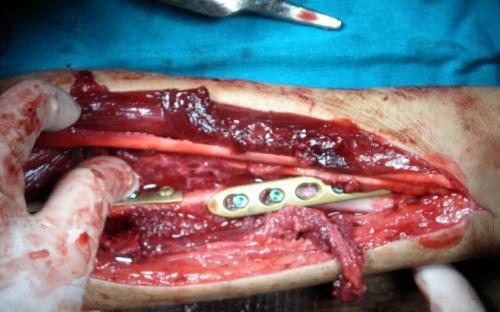

Άντρας 21 ετών υπέστη διπολικό κάταγμα της κερκίδας και κάταγμα της ωλένης, που αντιμετωπίστηκε σε περιφεριακό νοσοκομείο. 9 μήνες μετά διαπιστώθηκε ψευδάρθρωση της κερκίδας με οστικό απόλυμα 6,5 εκ. Αντιμετωπίστηκε με τη χρήση αγγειούμενης περόνης, η οποία γεφύρωσε το οστικό έλλειμμα της κερκίδας.